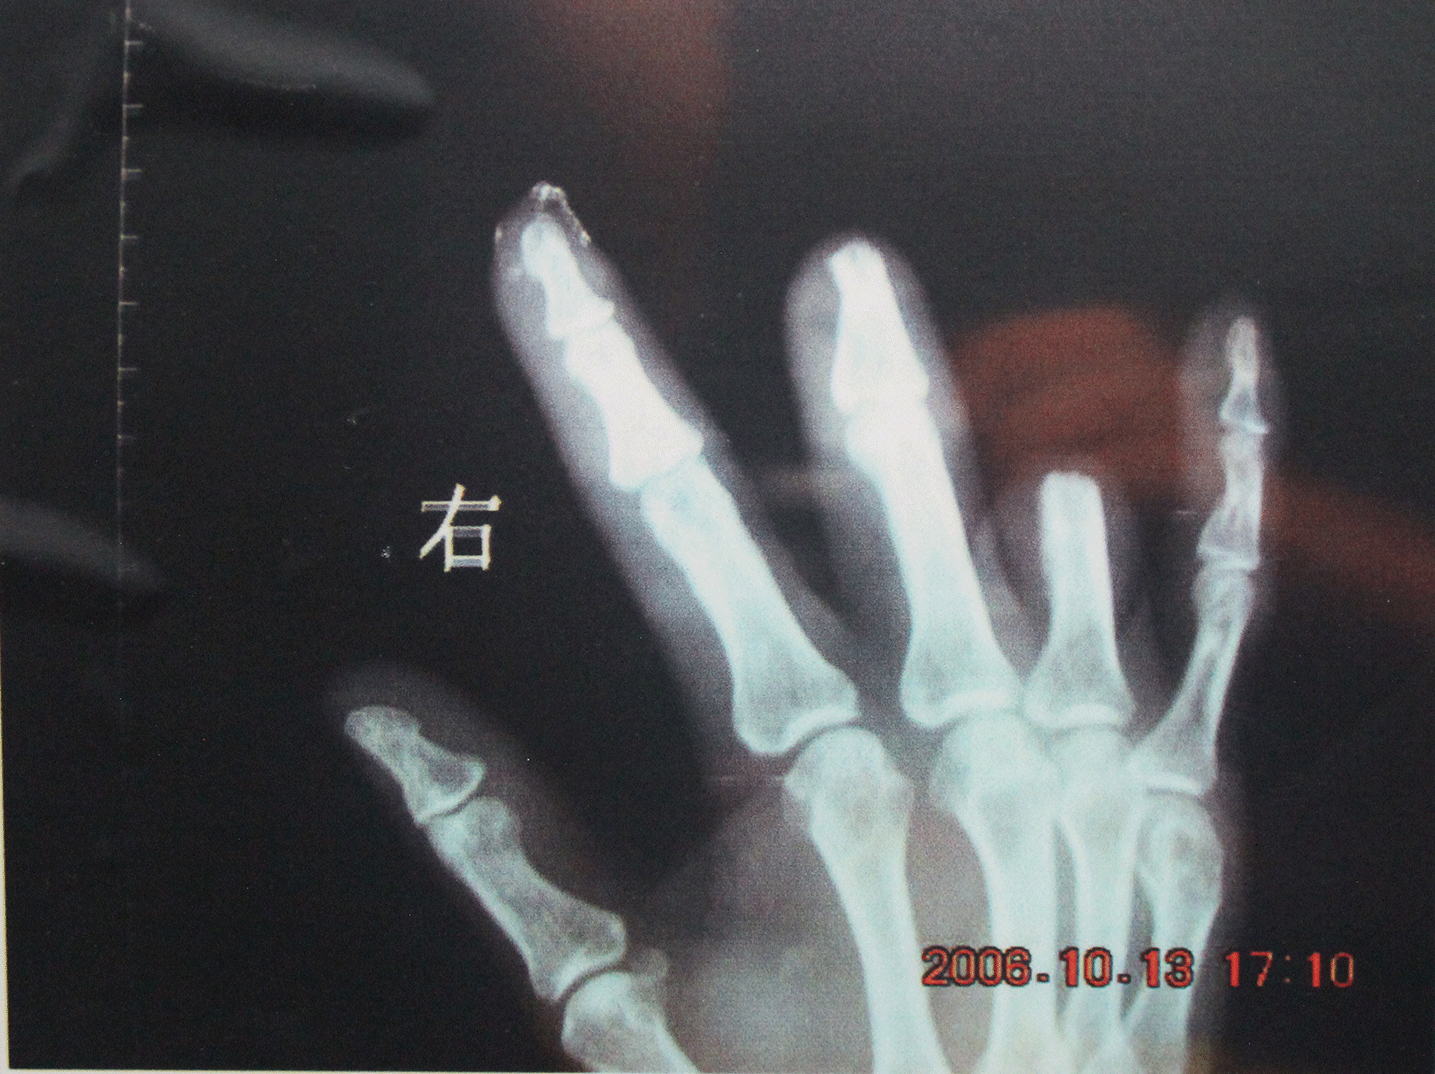

每年珠三角估计发生断指事故个案至少有3万宗,被机器切断的手指头则超过4万只!

我永远记得今年(2008)的9月3号,我在厂里工作,却被800千牛式侧压机压到了右手。食指、中指、无名指木端都被冲断了,送到医院后医生帮我接了上去,指上插满了钢针、还缝了一百多针,但没几天医生就告诉我中指末端没有接活,因此不得不做第二次手术把中指锯掉了一截,而我的食指和无名指虽然接活了,却短了一截,而且再也伸不直了、握不紧了。